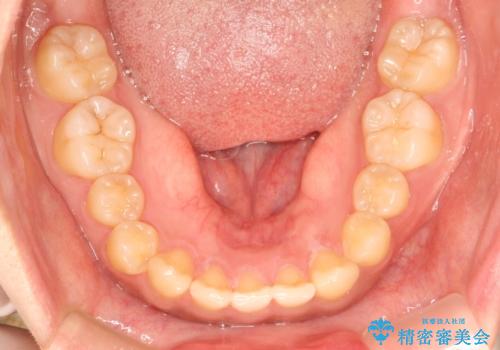

前歯の隙間を閉じたい。インビザラインによる治療

- 前歯の隙間を閉じたいと矯正カウンセリングに来られた患者様です。

マウスピース矯正(インビザライン)を行い短期間で治療が完了しました。